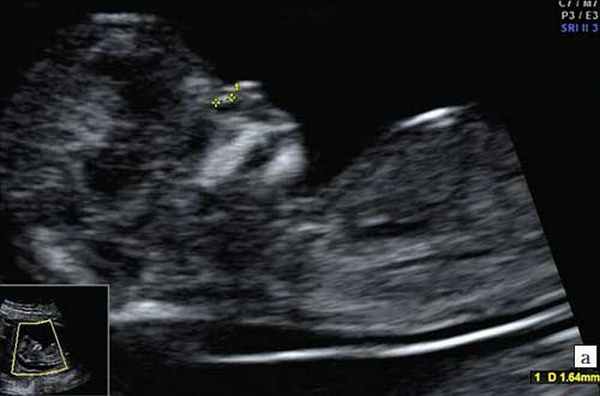

1. Ниже на УЗИ мы видим нормальную носовую кость. Можно различить 3 четкие линии.

2. Гипоплазия носовой кости. УЗИ сделано на 12 неделе беременности. Длина — 1,4 мм (ниже границы нормы).